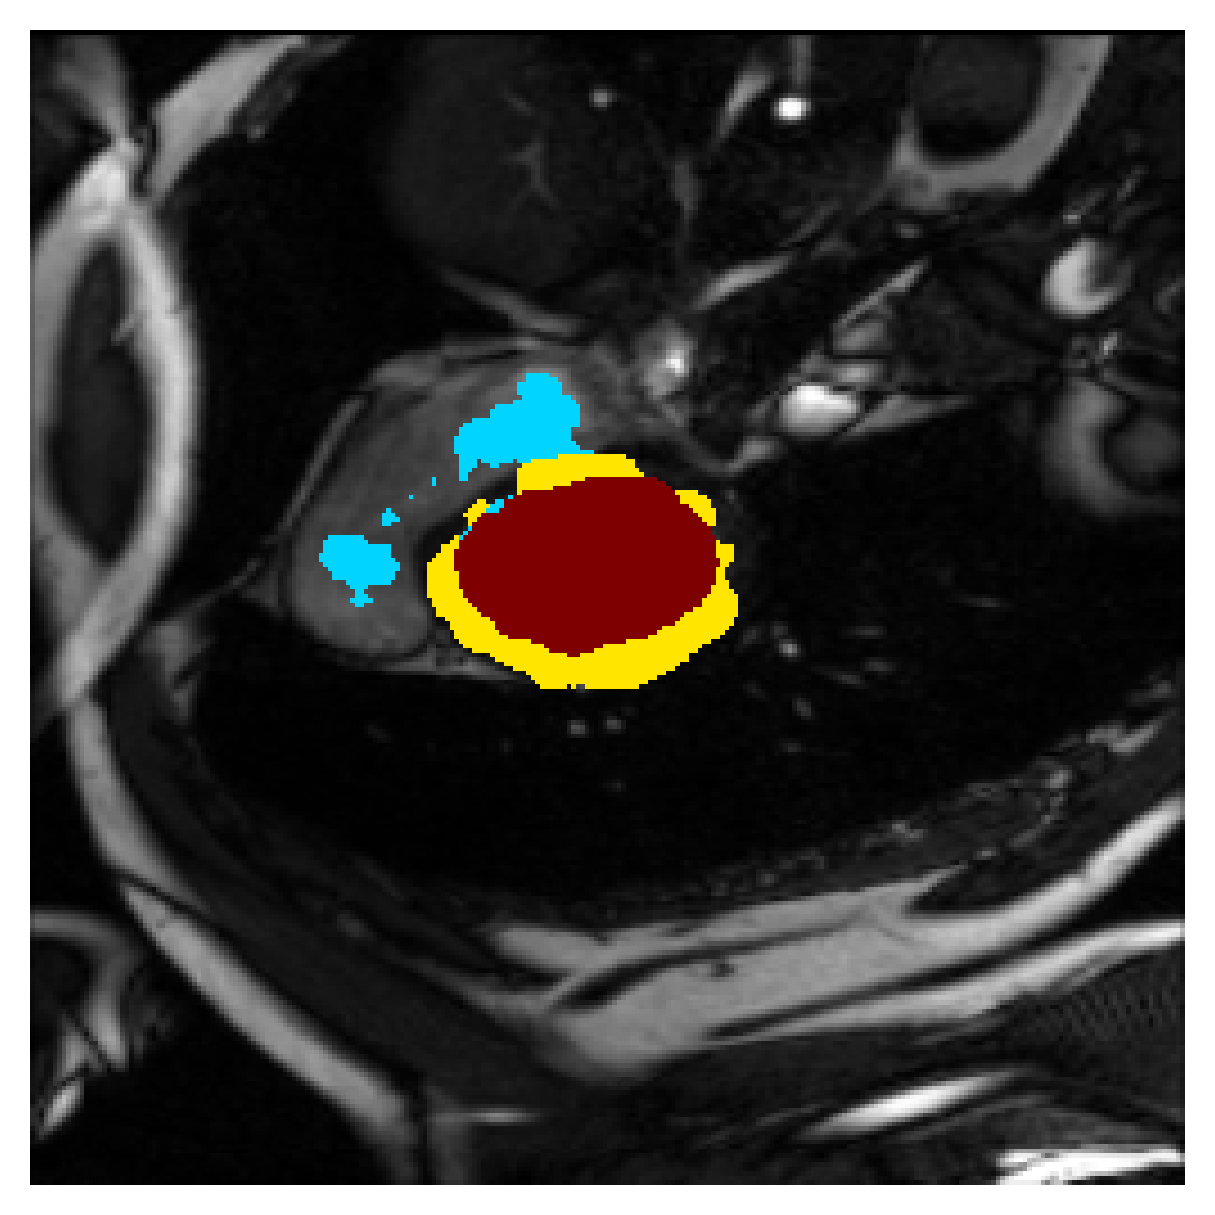

Qualitative comparison

| (a) Ground truth | (b) , full | (c) , weak | (d) |

| (full) | supervision | supervision | |

| (e) | (f) | (g) | (h) CRF-loss |

In Figure 6 we provide qualitative results on a number of randomly chosen test set slices. Upon visual inspection, we can observe that training with the intensity-aware distances (particularly with and ) follows the image gradients better and is better at recovering the underlying shape than the Euclidean version. The CRF-loss seems to recover the shape of the myocardium and left ventricle to some extent, but fails entirely on the right ventricle.